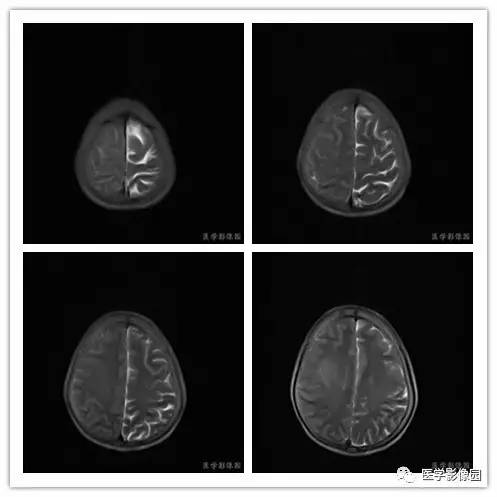

临床资料:女,59岁,于3月前无明显诱因出现左侧肢体乏力、记忆力下降,未行特殊处理,上述症状逐渐加重,并出现左侧面瘫。

影像学表现:右侧颞叶深部区见一长T1、长T2囊样信号,成明显环形强化、未见明确结节影,没有FLAIR和DWI图,内见分隔,边界较清,周围水肿不明显,右侧脑室明显受压、颞角扩大,右侧脑沟明显变浅,脑中线结果向左偏移。

结果 血管外皮细胞瘤

MR影像表现上有如下特点:

1.肿瘤主要表现为等长T1 、等长T2 混杂信号影,偶可见短T1 或短T2 信号影,注药后,肿瘤增强明显但不均匀;

2.外形呈不规则分叶状;

3.半数以上的肿瘤与硬膜窄基底相连;

4.肿瘤内常可见血管流空影而见不到钙化影;

5.肿瘤附近骨质可见破坏而见不到增生硬化。